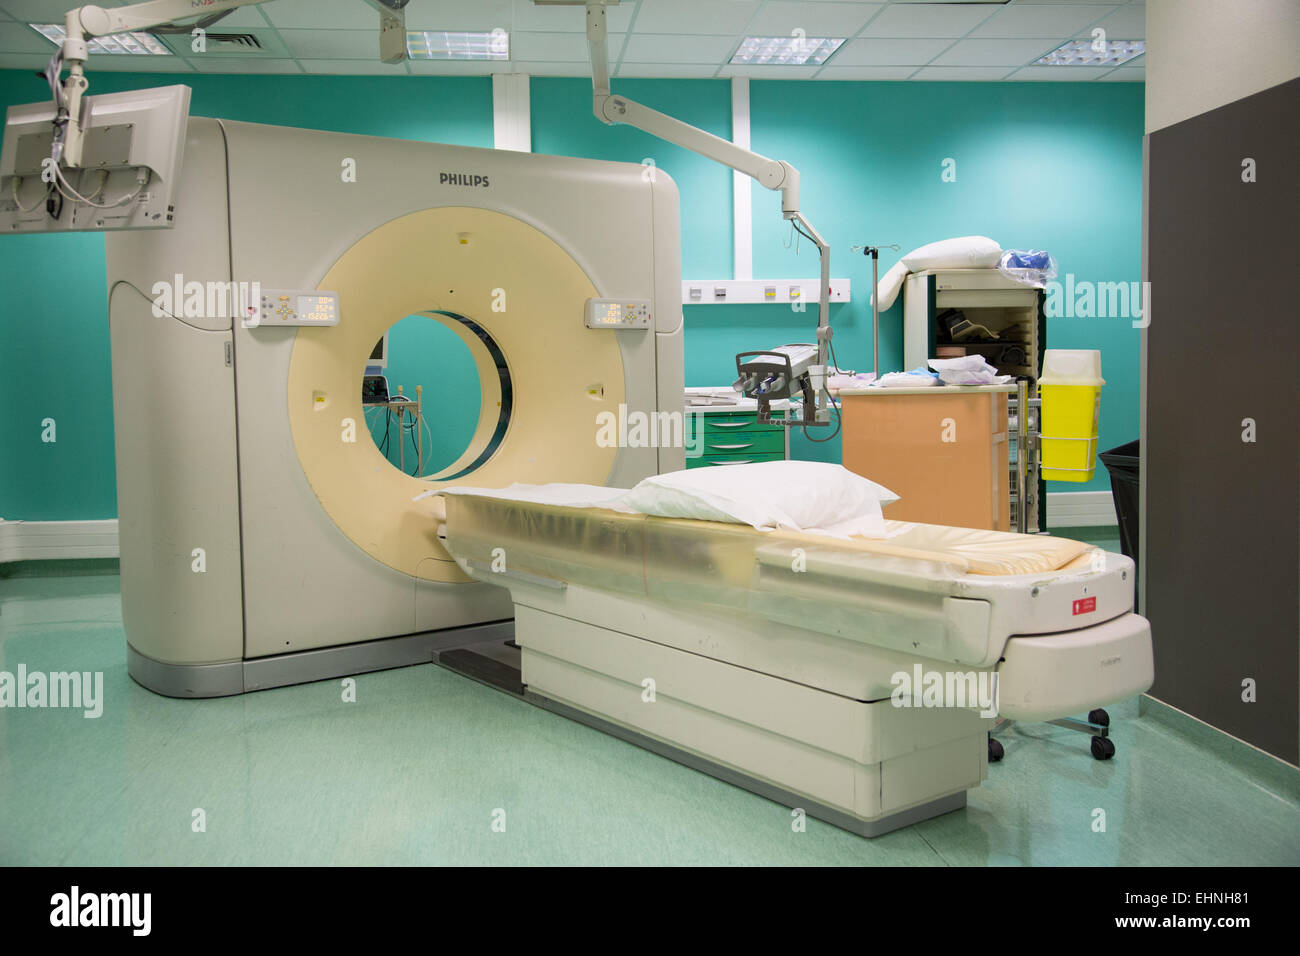

CT-scan. Stock Photohttps://www.alamy.com/image-license-details/?v=1https://www.alamy.com/stock-photo-ct-scan-79765167.html

CT-scan. Stock Photohttps://www.alamy.com/image-license-details/?v=1https://www.alamy.com/stock-photo-ct-scan-79765167.htmlRMEHNH7Y–CT-scan.

CT-scan. Stock Photohttps://www.alamy.com/image-license-details/?v=1https://www.alamy.com/stock-photo-ct-scan-79765169.html

CT-scan. Stock Photohttps://www.alamy.com/image-license-details/?v=1https://www.alamy.com/stock-photo-ct-scan-79765169.htmlRMEHNH81–CT-scan.